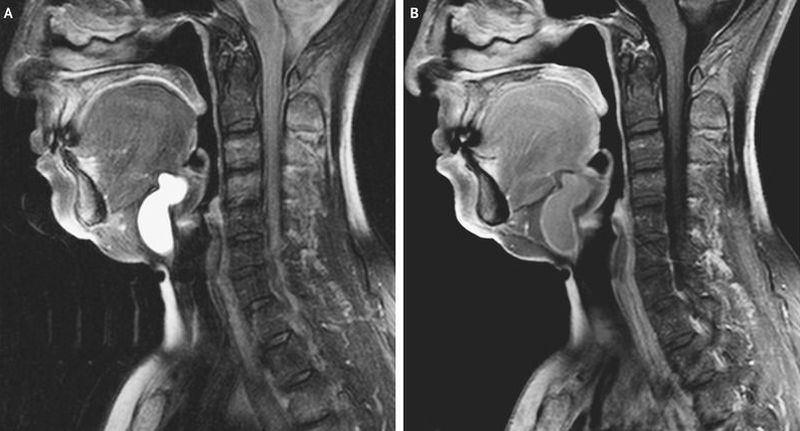

A 68-year-old woman presented to the otorhinolaryngology clinic with a 5-year history of swelling in the neck and the recent development of discomfort when she swallowed. On physical examination, she had a soft and nontender mass in the midline of the neck that moved with protrusion of the tongue and swallowing. Examination with a nasopharyngoscope was normal, and ultrasonography of the neck showed a normal-appearing thyroid gland. Sagittal T2-weighted magnetic resonance imaging (MRI) of the neck revealed a hyperintense cyst in the midline, posterior to the hyoid bone and anterior to the thyroid cartilage (Panel A). T1-weighted MRI with gadolinium enhancement revealed a well-encapsulated cyst that contained fluid (Panel B). A thyroglossal duct cyst, the most common congenital cyst of the neck, was diagnosed. The patient underwent surgical removal of the cyst, and pathological examination showed no evidence of associated infection. The patient did well after surgery and had complete resolution of her presenting symptoms.